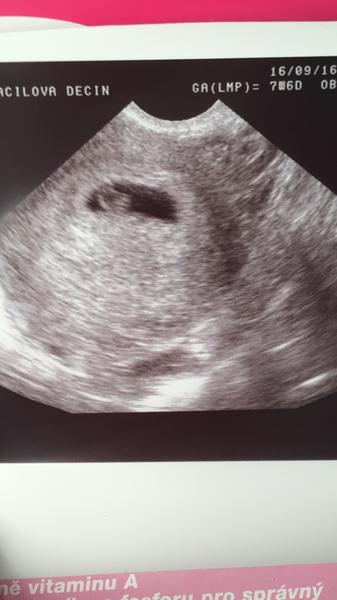

na tej fotke mas napisane GA(LMP) = 7+6, to znamena ze gestacny vek od poslednej MS bol v piatok 7 tyzdnov a 6 dni. Tym padom 6 tyzdnov o ktorych hovoris je od otehotnenia, nie od poslednej menstruacie.. to vysvetluje aj preco uz bolo vidiet srdiecko 🙂 takto to uz vychadza?

Na netu je mraky kalkulaček, které vypočítají délku těhotenství podle 1. dne menstruace. Vychází to pak tak, jak píše @bbubble. Pokud je 23. 7. první den poslední menstruace, jsi dnes např. podle této kalkulačky (http://www.maminkam.cz/tehotenska-kalkulacka#fo...) na začátku probíhajícího 9. týdne, přesně 8+1. Takže pokud lékařka mluvila o šesti týdnech, počítala to opravdu podle okamžiku předpokládaného otěhotnění, ne podle menstruace.

Kdyz teda uz osmi týden tak mi ale přijde ze je to na ultrazvuku nějaké malinke .. Myslím ze i Ina místo říkala ze je to menší takze mohlo dojit k oplodnění trochu déle? Kdyz jsem koukala na fotky ultrazvuku v 8 týdnu tak uz je tam videt víc a ne jen to co mam ja .